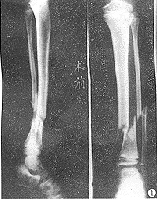

胫骨位置表浅,局部症状明显,加上X线检查,诊断并不困难。但应注意骨折的合并症,仔细检查软组织损伤程度,及时发现症状,及时处理。

x线检查在胫腓骨骨折中用于诊断、估计骨折愈合的程度、发现骨折的并发症及、做必要的鉴别诊断。

在临床上,一旦怀疑有胫腓骨骨折,就要拍摄小腿正侧位的X线片,照片质量要求较高,除了能发现明显骨折外,对怀疑的线状裂纹也要确定,因为线状骨折也影响愈后和治疗,如行内固定,其稳定性要把线状骨折的因素考虑在内。

在晚期估计其愈合的程度时,有时要拍摄透过骨折端的斜位片。复位后的x线片最好包括膝、踝两个关节,以确定这两个关节轴线在平行的位置,防止晚期因膝、踝关节面的不平行而造成的并发症。原则上拍小腿x线片时要包括胫腓骨的全长。以防止低位胫骨骨折,合并有高位的腓骨骨折发生漏诊。

在骨的x线描述上,首先确定骨折的部位,在上l/3、中l/3或下1/3。再确定骨折类型是横断、斜行或螺旋型骨折,骨折有无粉碎,以及是否多段。侧方移位严重则愈合很难。×线片上不易确定上下骨折段的旋转移位,要从临床上来判断和纠正。

X线正位片应包括胫腓骨全长,以免漏诊。X线可见骨折线、碎骨片、断端移位等。